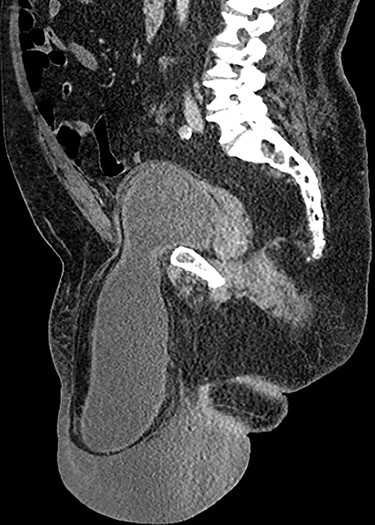

Computed tomography (CT) scan of the abdomen and pelvis with contrast revealed a large right indirect inguinal hernia containing a significant portion of the bladder within the scrotum (Figs 1–3). There was associated bilateral hydronephrosis and hydroureter, and significant scrotal oedema seen within the soft tissues.

Sagittal CT image of the abdomen and pelvis demonstrating herniation of the bladder into the scrotum.